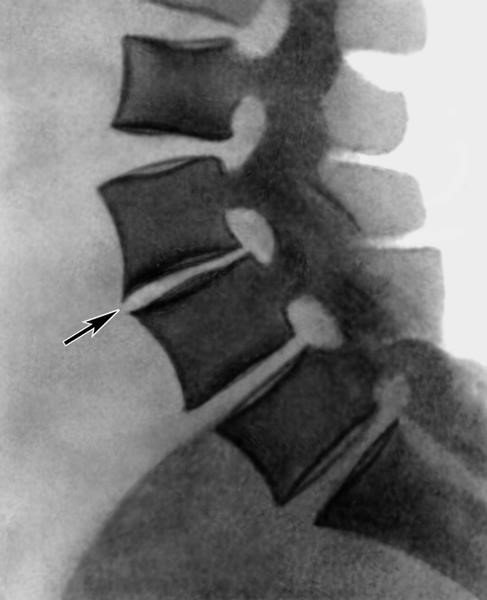

Обнаружить заболевание можно на рентгеновском снимке. Одним из характерных признаков этого заболевания является уменьшение болевых ощущений или их прекращение при наклоне человека вперед вниз, а также лежа в позе эмбриона. В таких положениях снимается нагрузка на передний продольный связочный отдел позвоночника, и человеку становится легче.

Одной из особенностей данного заболевания является возможность самоизлечения, благодаря сращиванию остеофитов, что на рентгеновском снимке выглядит как костный блок нескольких позвонков. Люди, страдающие сахарным диабетом, попадают в группу риска возникновения спондилеза. У них может возникнуть одна из разновидностей этого заболевания – болезнь Ферсье.

При обследовании обнаруживается гипотрофия мышц поясничного отдела позвоночника. Иногда эта болезнь поражает и шейный отдел. Рентген показывает, что отслаивается передняя продольная связка позвоночного столба.